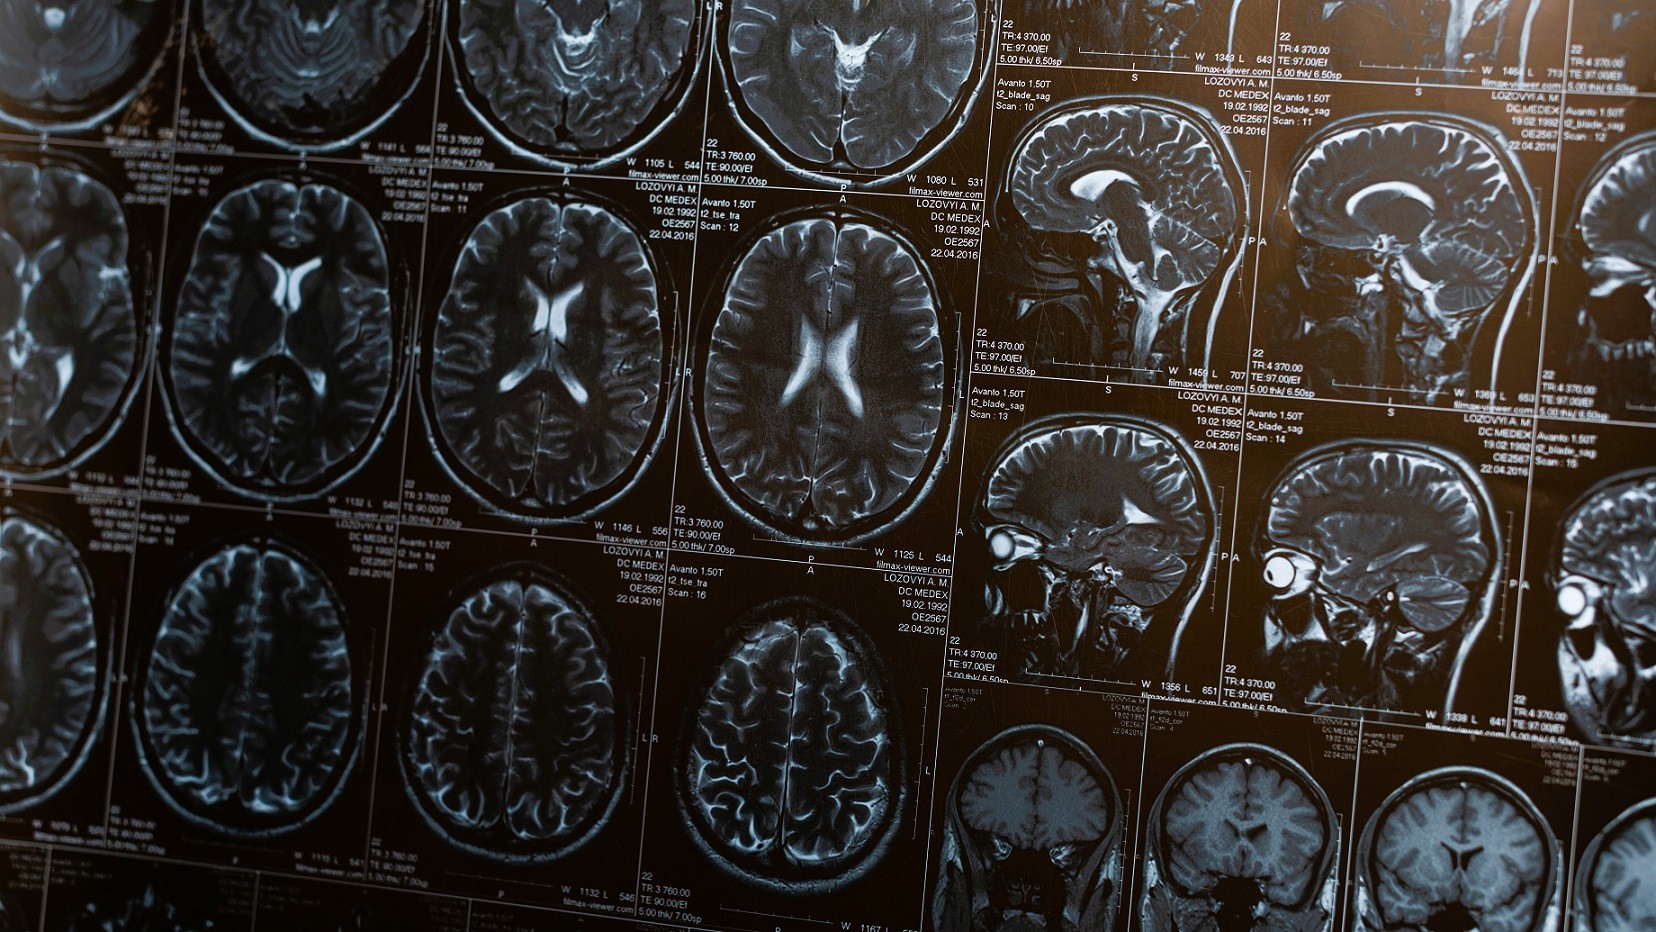

Disse data vil så blive sammenlignet med testpersonernes hjerneskanninger og kognitive test for at undersøge, om der f.eks. er en sammenhæng mellem bestemte pesticider og en øget forekomst af demenssygdomme.